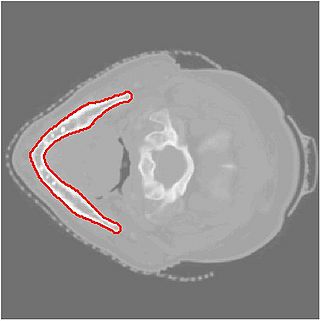

Final Segmentation

• First structure of interest is the mandible, by the end of the project week, obtain its segmentation

• Segmentation results are shown above.